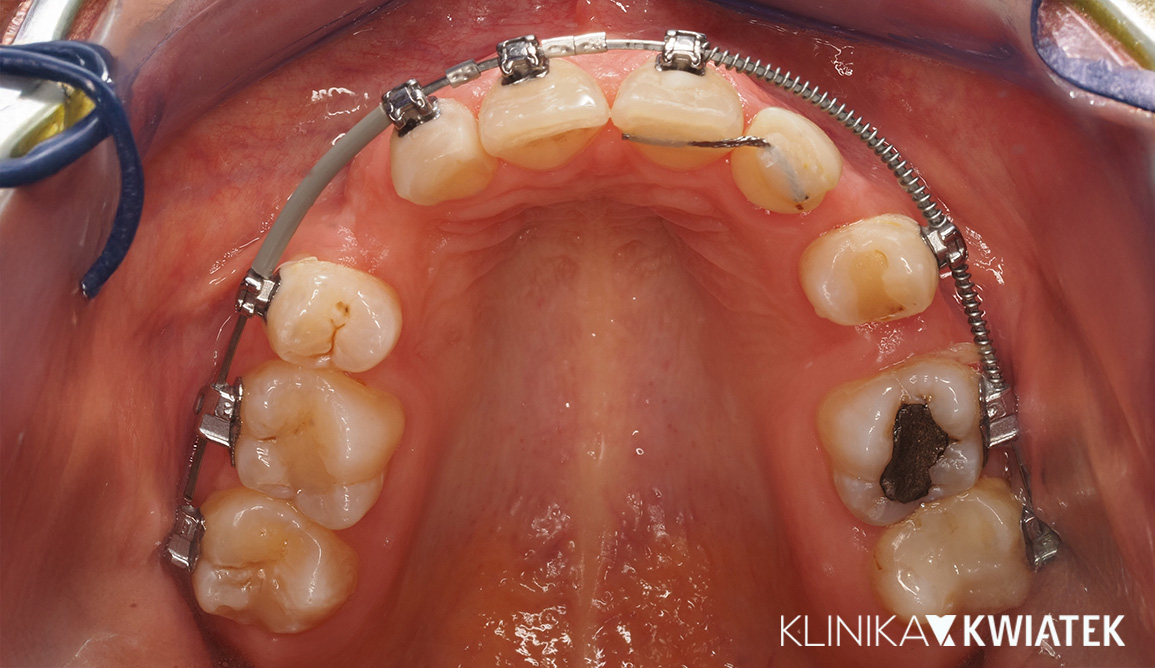

Kompleksowa przemiana: ortodoncja, protetyka i estetyka w jednej terapii

Do naszej kliniki zgłosił się Pacjent z rozległymi problemami stomatologicznymi - od złej higieny i stany zapalne, aż po złożoną wadę zgryzu wpływającą na estetykę i funkcję. Po wykonaniu pełnej diagnostyki wprowadzono wieloetapowy plan leczenia: higienizacje, leczenie zachowawcze, endodontyczne, ekstrakcje, rozbudowane leczenie ortodontyczne z zastosowaniem miniimplantów oraz finalną odbudowę estetyczną metodą flow injection.

Efektem jest harmonijny, jasny i zdrowy uśmiech oraz stabilna, fizjologiczna okluzja.